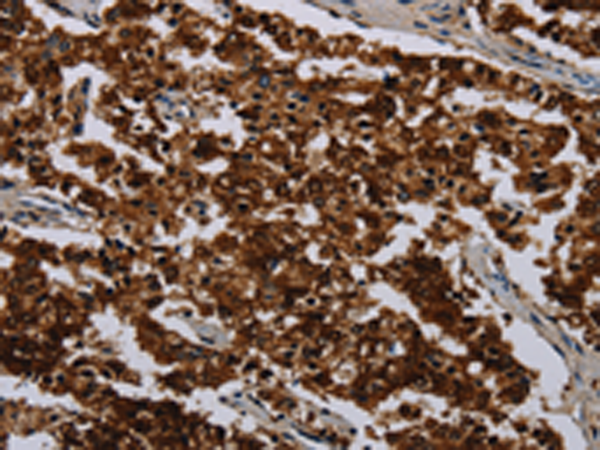

分类: 科研抗体货号: P08427别名: IDH; IDP; IDHM; IDPM; ICD-M; D2HGA2; mNADP-IDH应用: WB,IHC反应种属: Human, Mouse, Rat